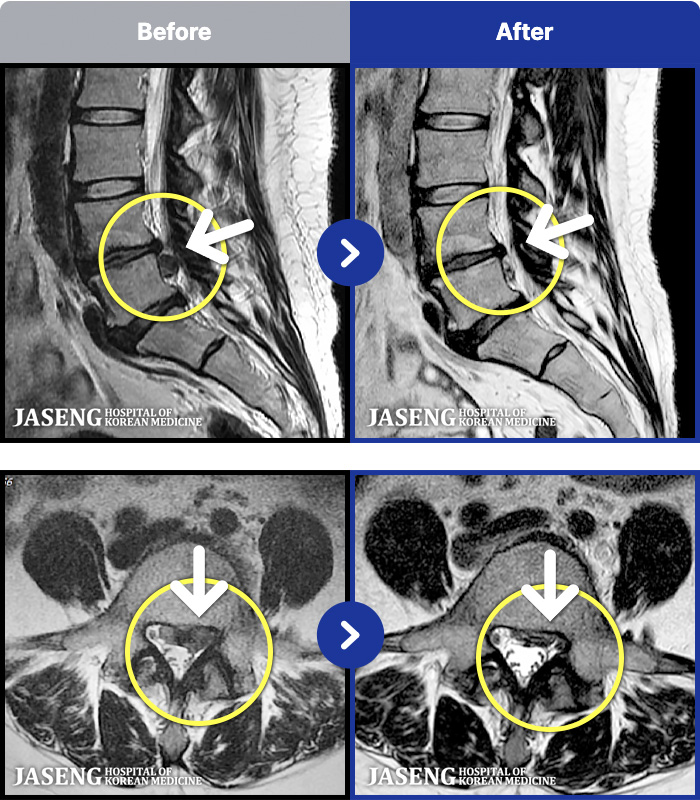

MRI ġ

MRI ũ ʸ Ȯϼ.

㸮 ؼ ̱ ư ϴ.